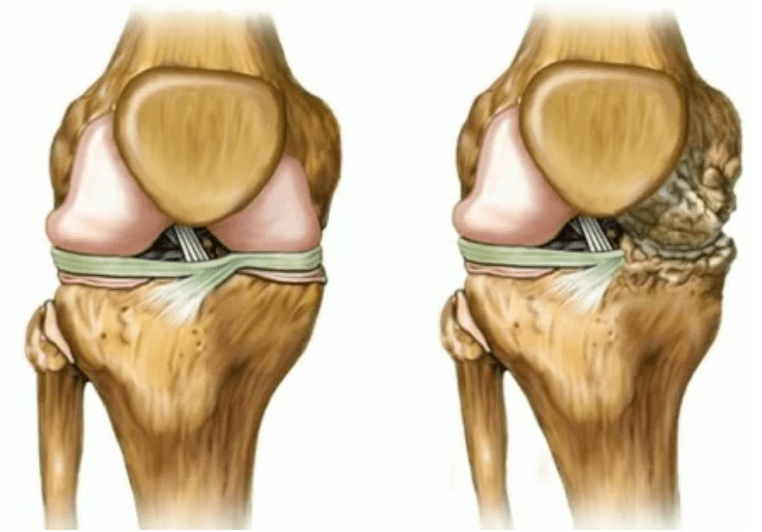

- Reducindo a fenda na fenda da articulación, que se fai notable na imaxe. A etapa da violación é determinada polo-tantenólogo diagnóstico. O paciente sente a complexidade ou a incapacidade de endereitar completamente e dobrar a extremidade;

- A deformación conxunta, a cartilaxe adquire unha forma irregular, provocando curvatura;

- Deterioro no estado do paciente con destrución completa da articulación.